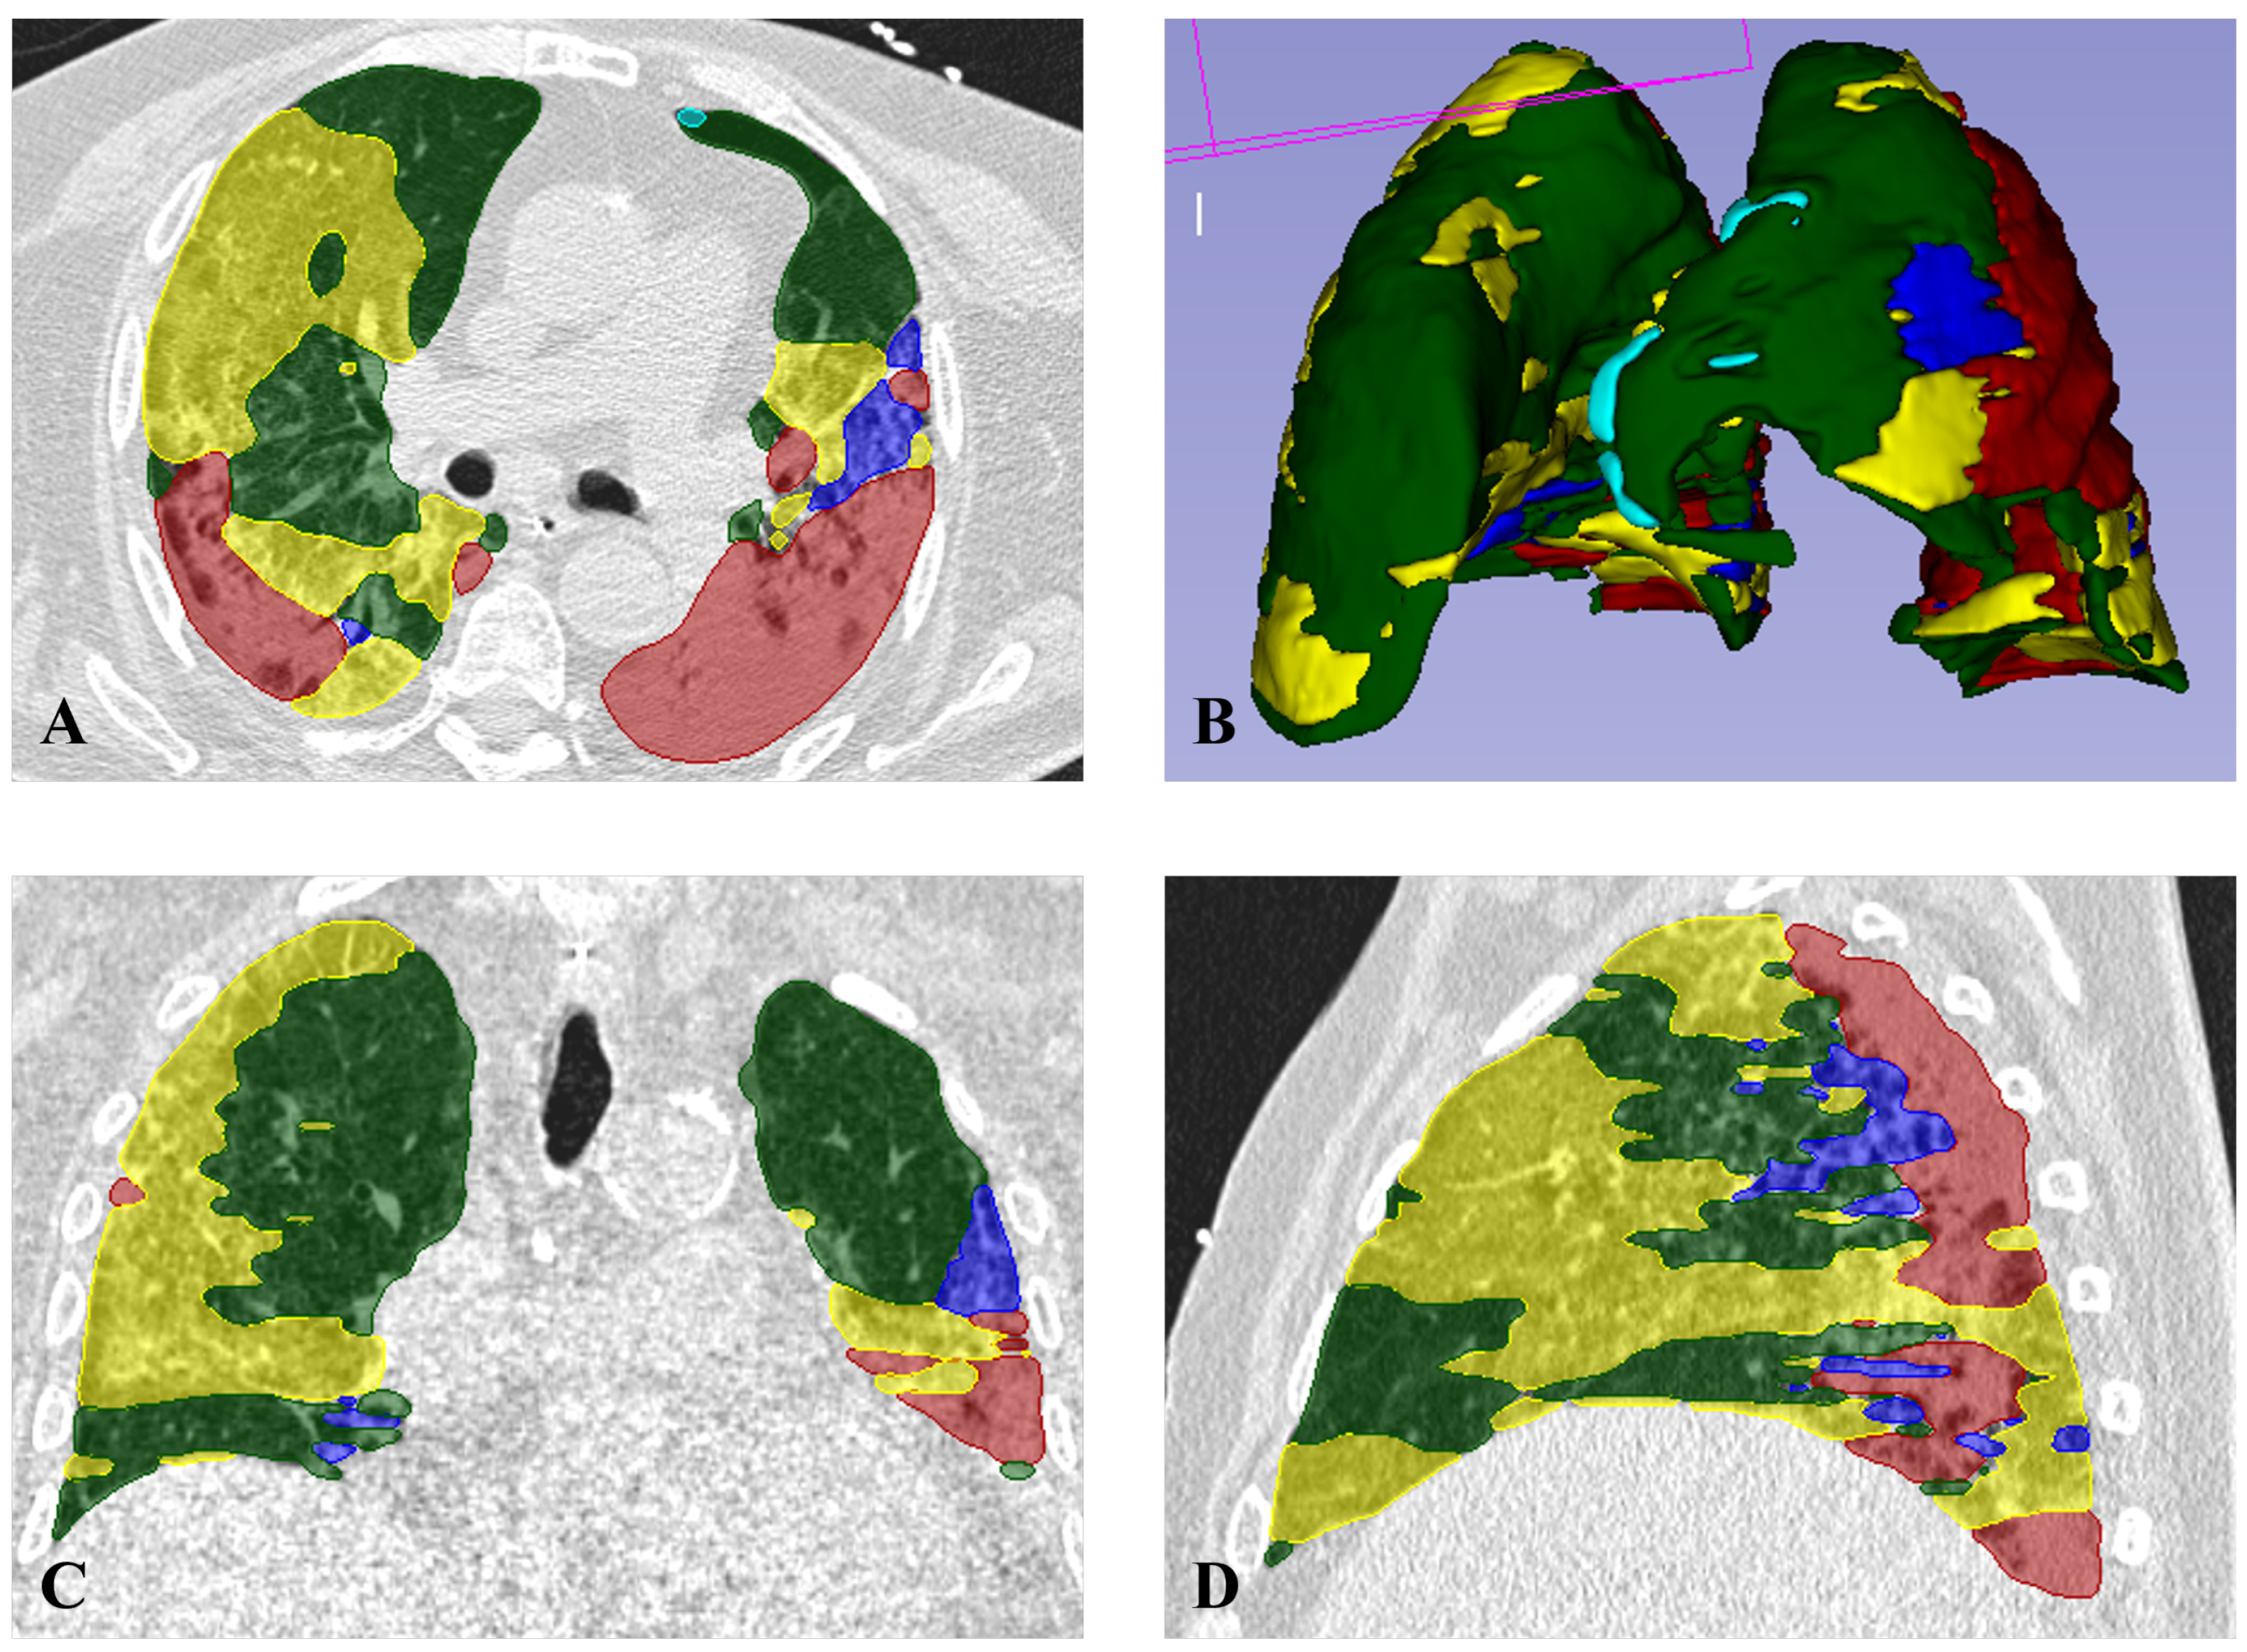

2.3. Radiomic Features Collection

2.4. Machine Learning Pipeline